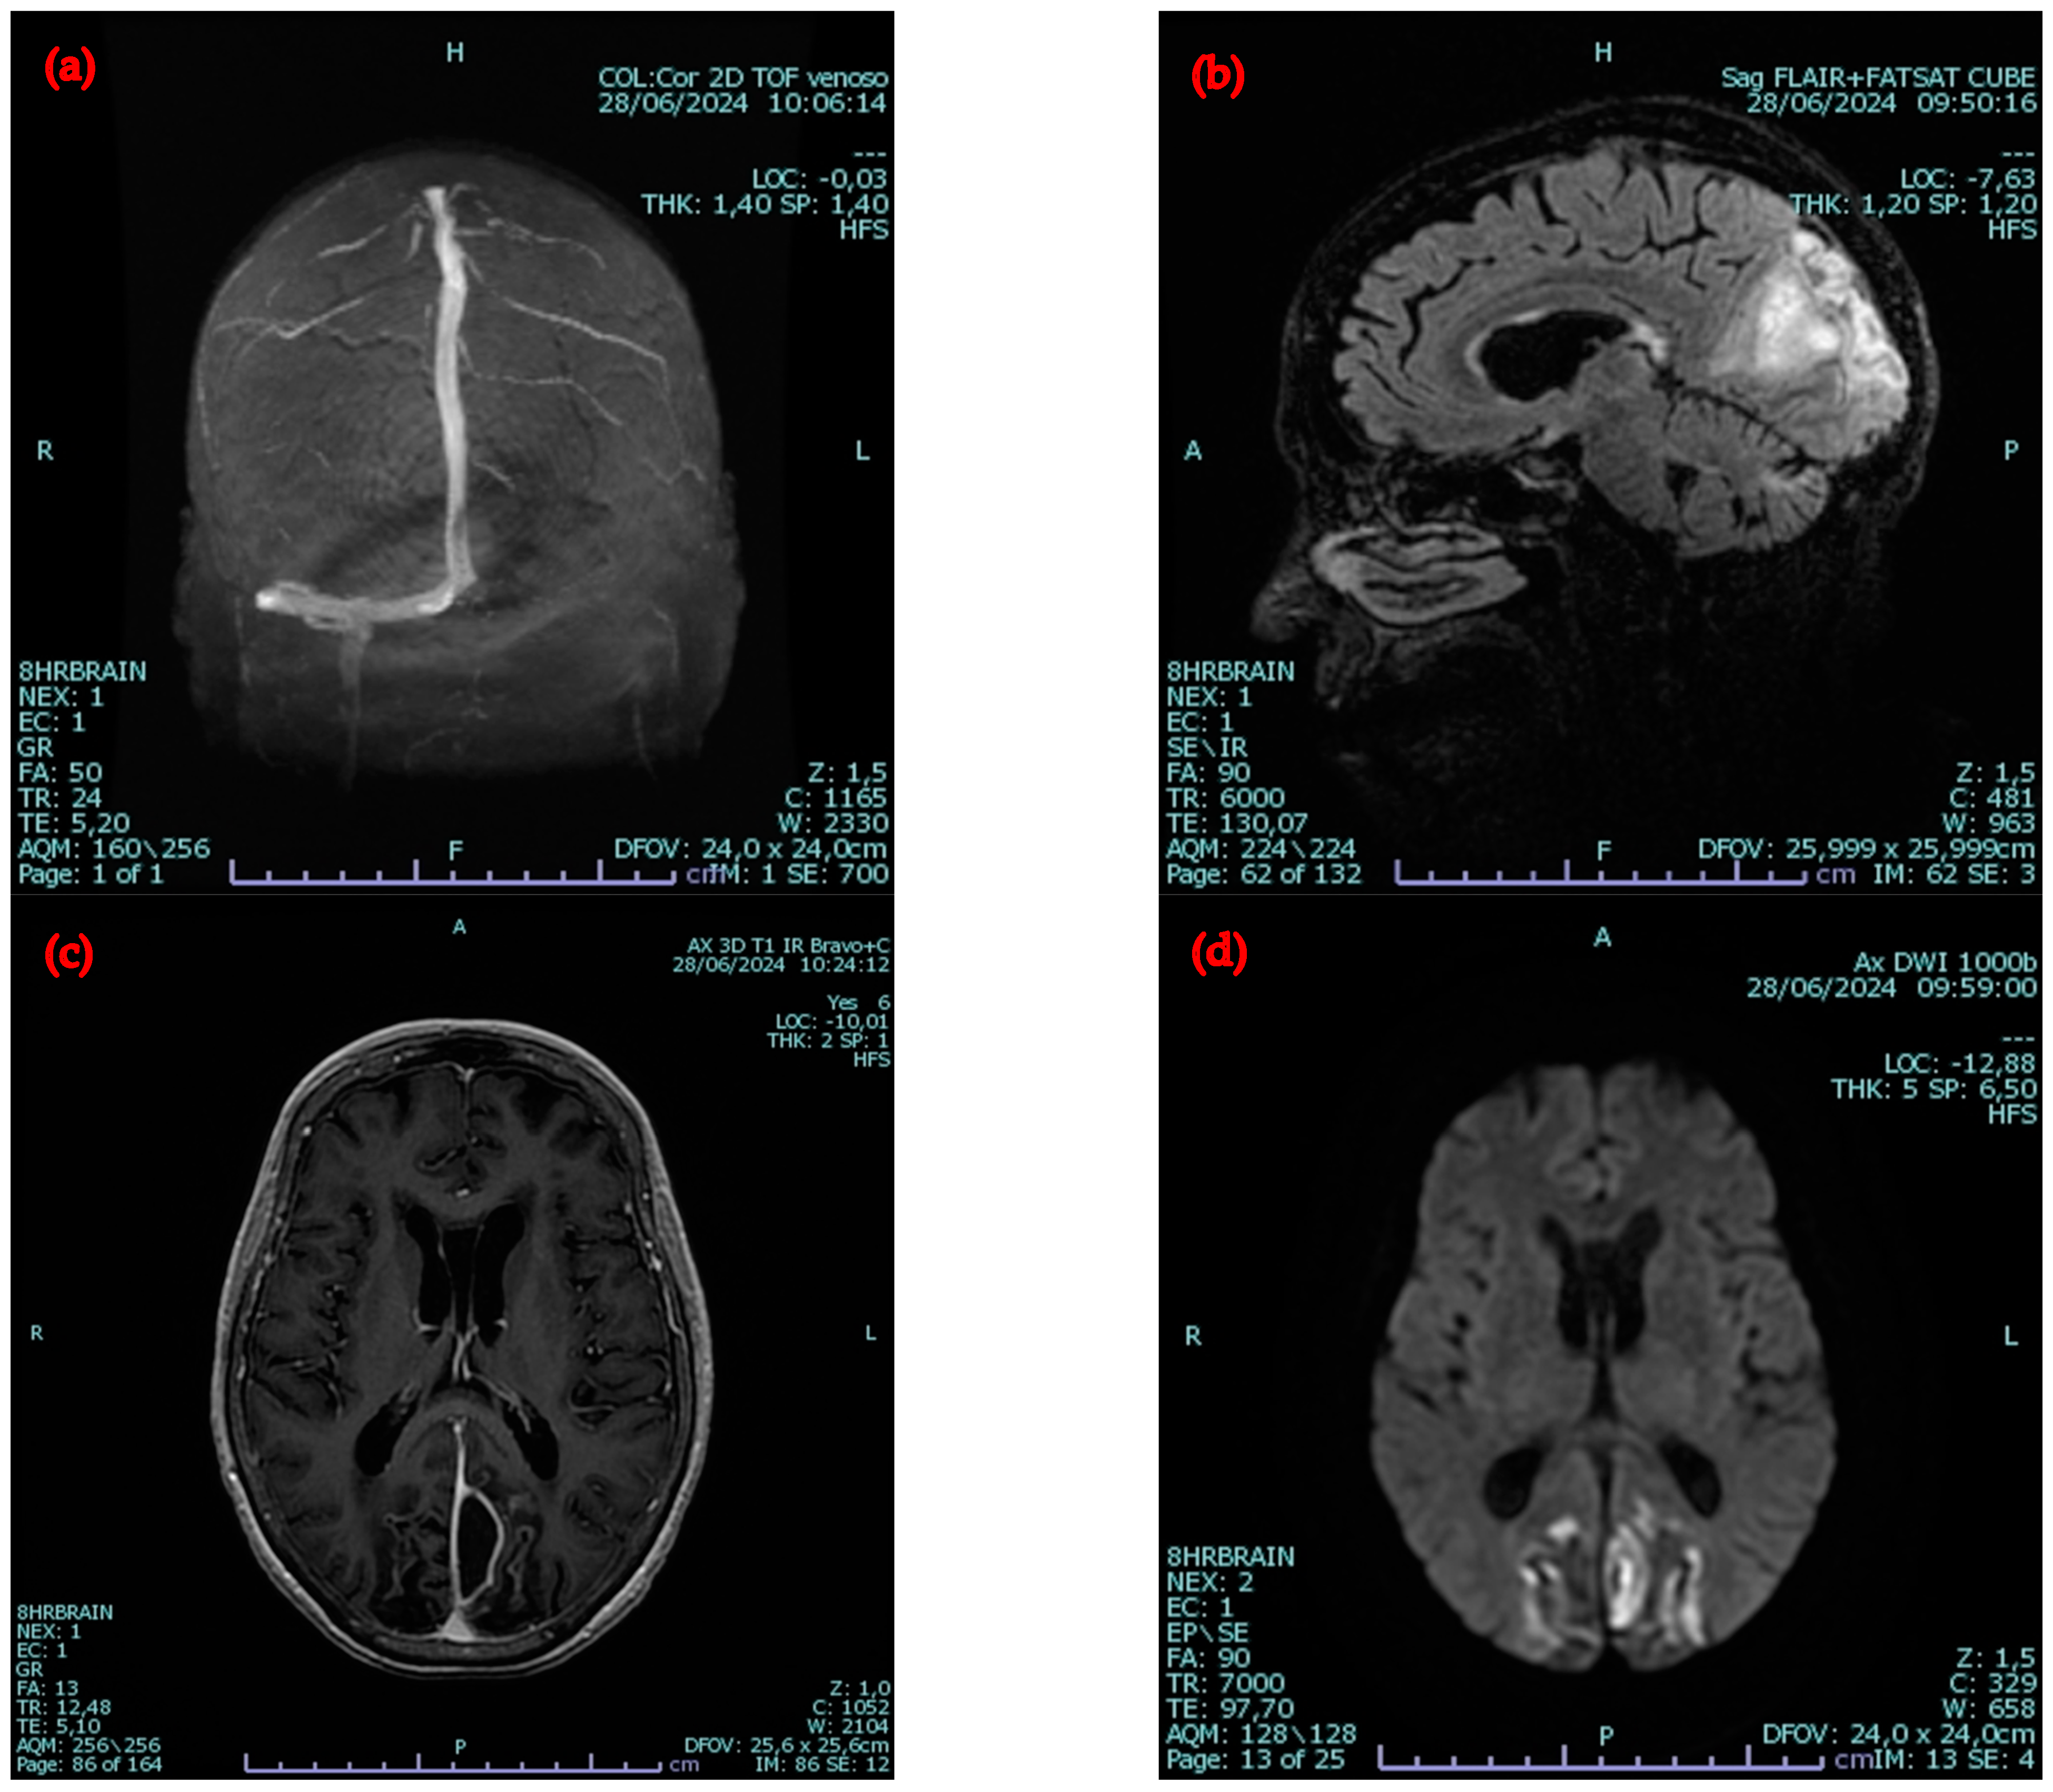

2.2. Second Admission to the Same Hospital

2.3. Admission to the Infectious Diseases Unit of Our University Hospital